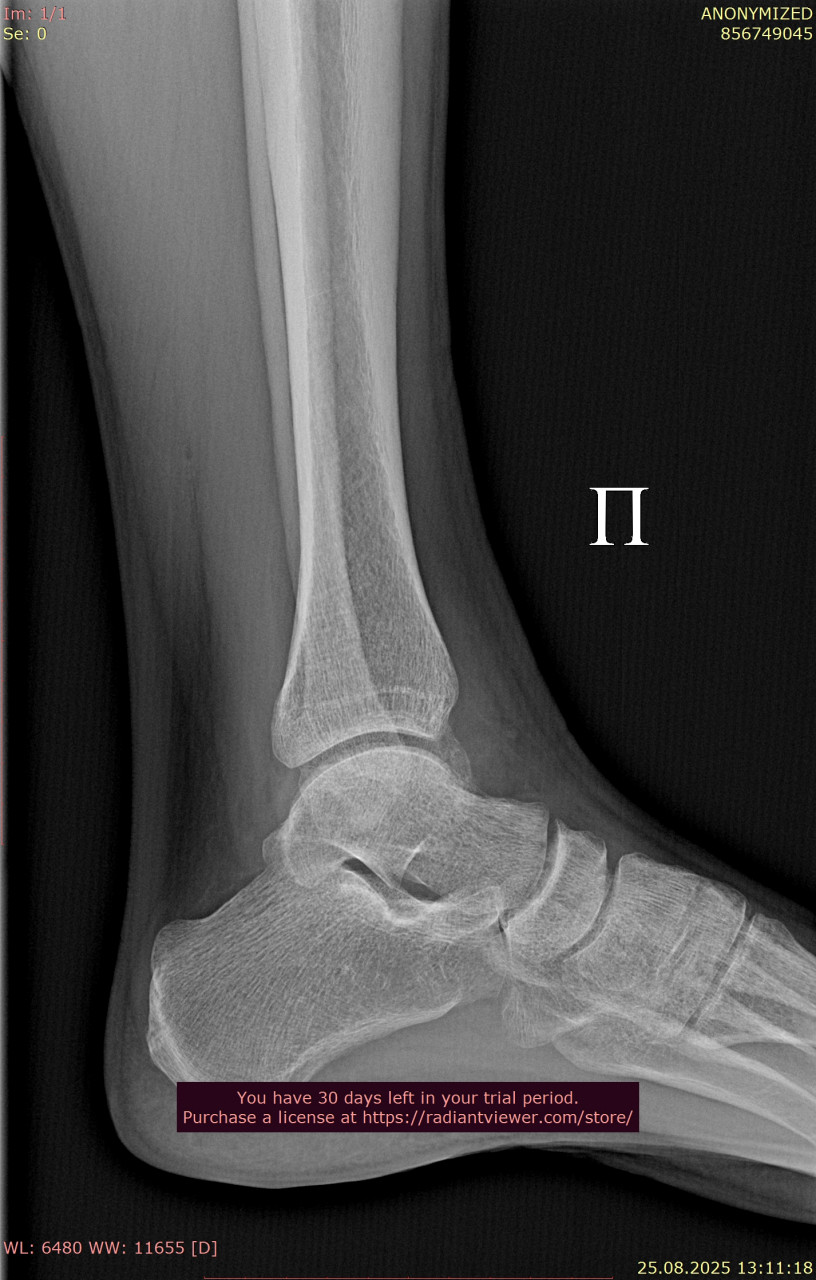

Посмотрите, пожалуйста, еще раз снимки голеностопного сустава, от 23.06.2025, когда был перелом (прикрепляю только 1 проекцию из за лимита файлов на сайте) и от 25.08.2025. Нет ли избыточного разрастания костей в области внутренней лодыжки? Если есть, то какие могут быть последствия? На сегодняшний день боли и ограничения подвижности пока нет. Заранее спасибо!

Здравствуйте. По контрольным снимкам от 25.08 выраженного избыточного костного разрастания в области внутренней лодыжки не видно и отмечается формирование нормального костного мозоля. Если в дальнейшем появятся боли или ограничение движений это может указывать на избыточное разрастание, но сейчас сустав выглядит благополучно. Рекомендую продолжать наблюдение и выполнять ЛФК.